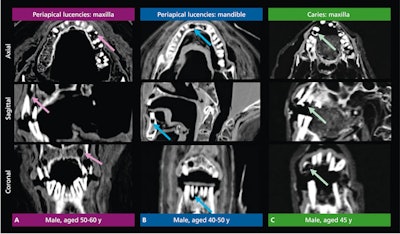

Figure 2: Periapical lucencies in the maxilla (purple arrows) (A) and mandible (blue arrows) (B) and caries (green arrows) (C) as viewed in the axial, sagittal, and coronal planes via computed tomography of three male mummies.

Using a database of computed tomography scans of 14 female mummies and 23 male mummies ranging in age from 19 to 60, researchers used imaging to search for decayed teeth and periapical lucencies. They also used the images to capture measurements from the cementoenamel junction to the alveolar crest. Regression analyses measured whether vascular disease was present.